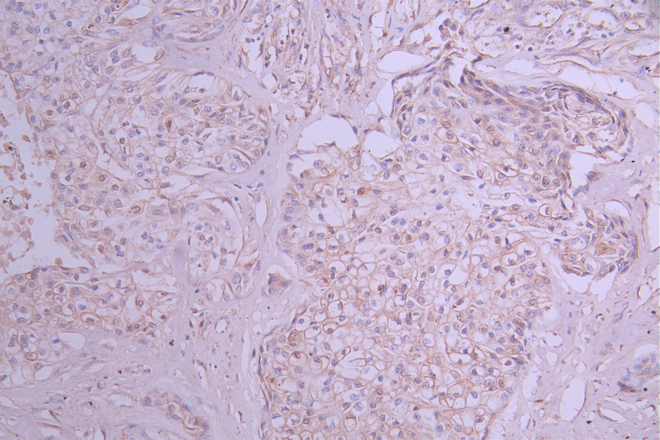

IHC image of CSB-RA079244A0HU diluted at 1:100 and staining in paraffin-embedded human pancreatic cancer performed on a Leica BondTM system. After dewaxing and hydration, antigen retrieval was mediated by high pressure in a citrate buffer (pH 6.0). Section was blocked with 10% normal goat serum 30min at RT. Then primary antibody (1% BSA) was incubated at 4°C overnight. The primary is detected by a Goat anti-rabbit polymer IgG labeled by HRP and visualized using 0.05% DAB.